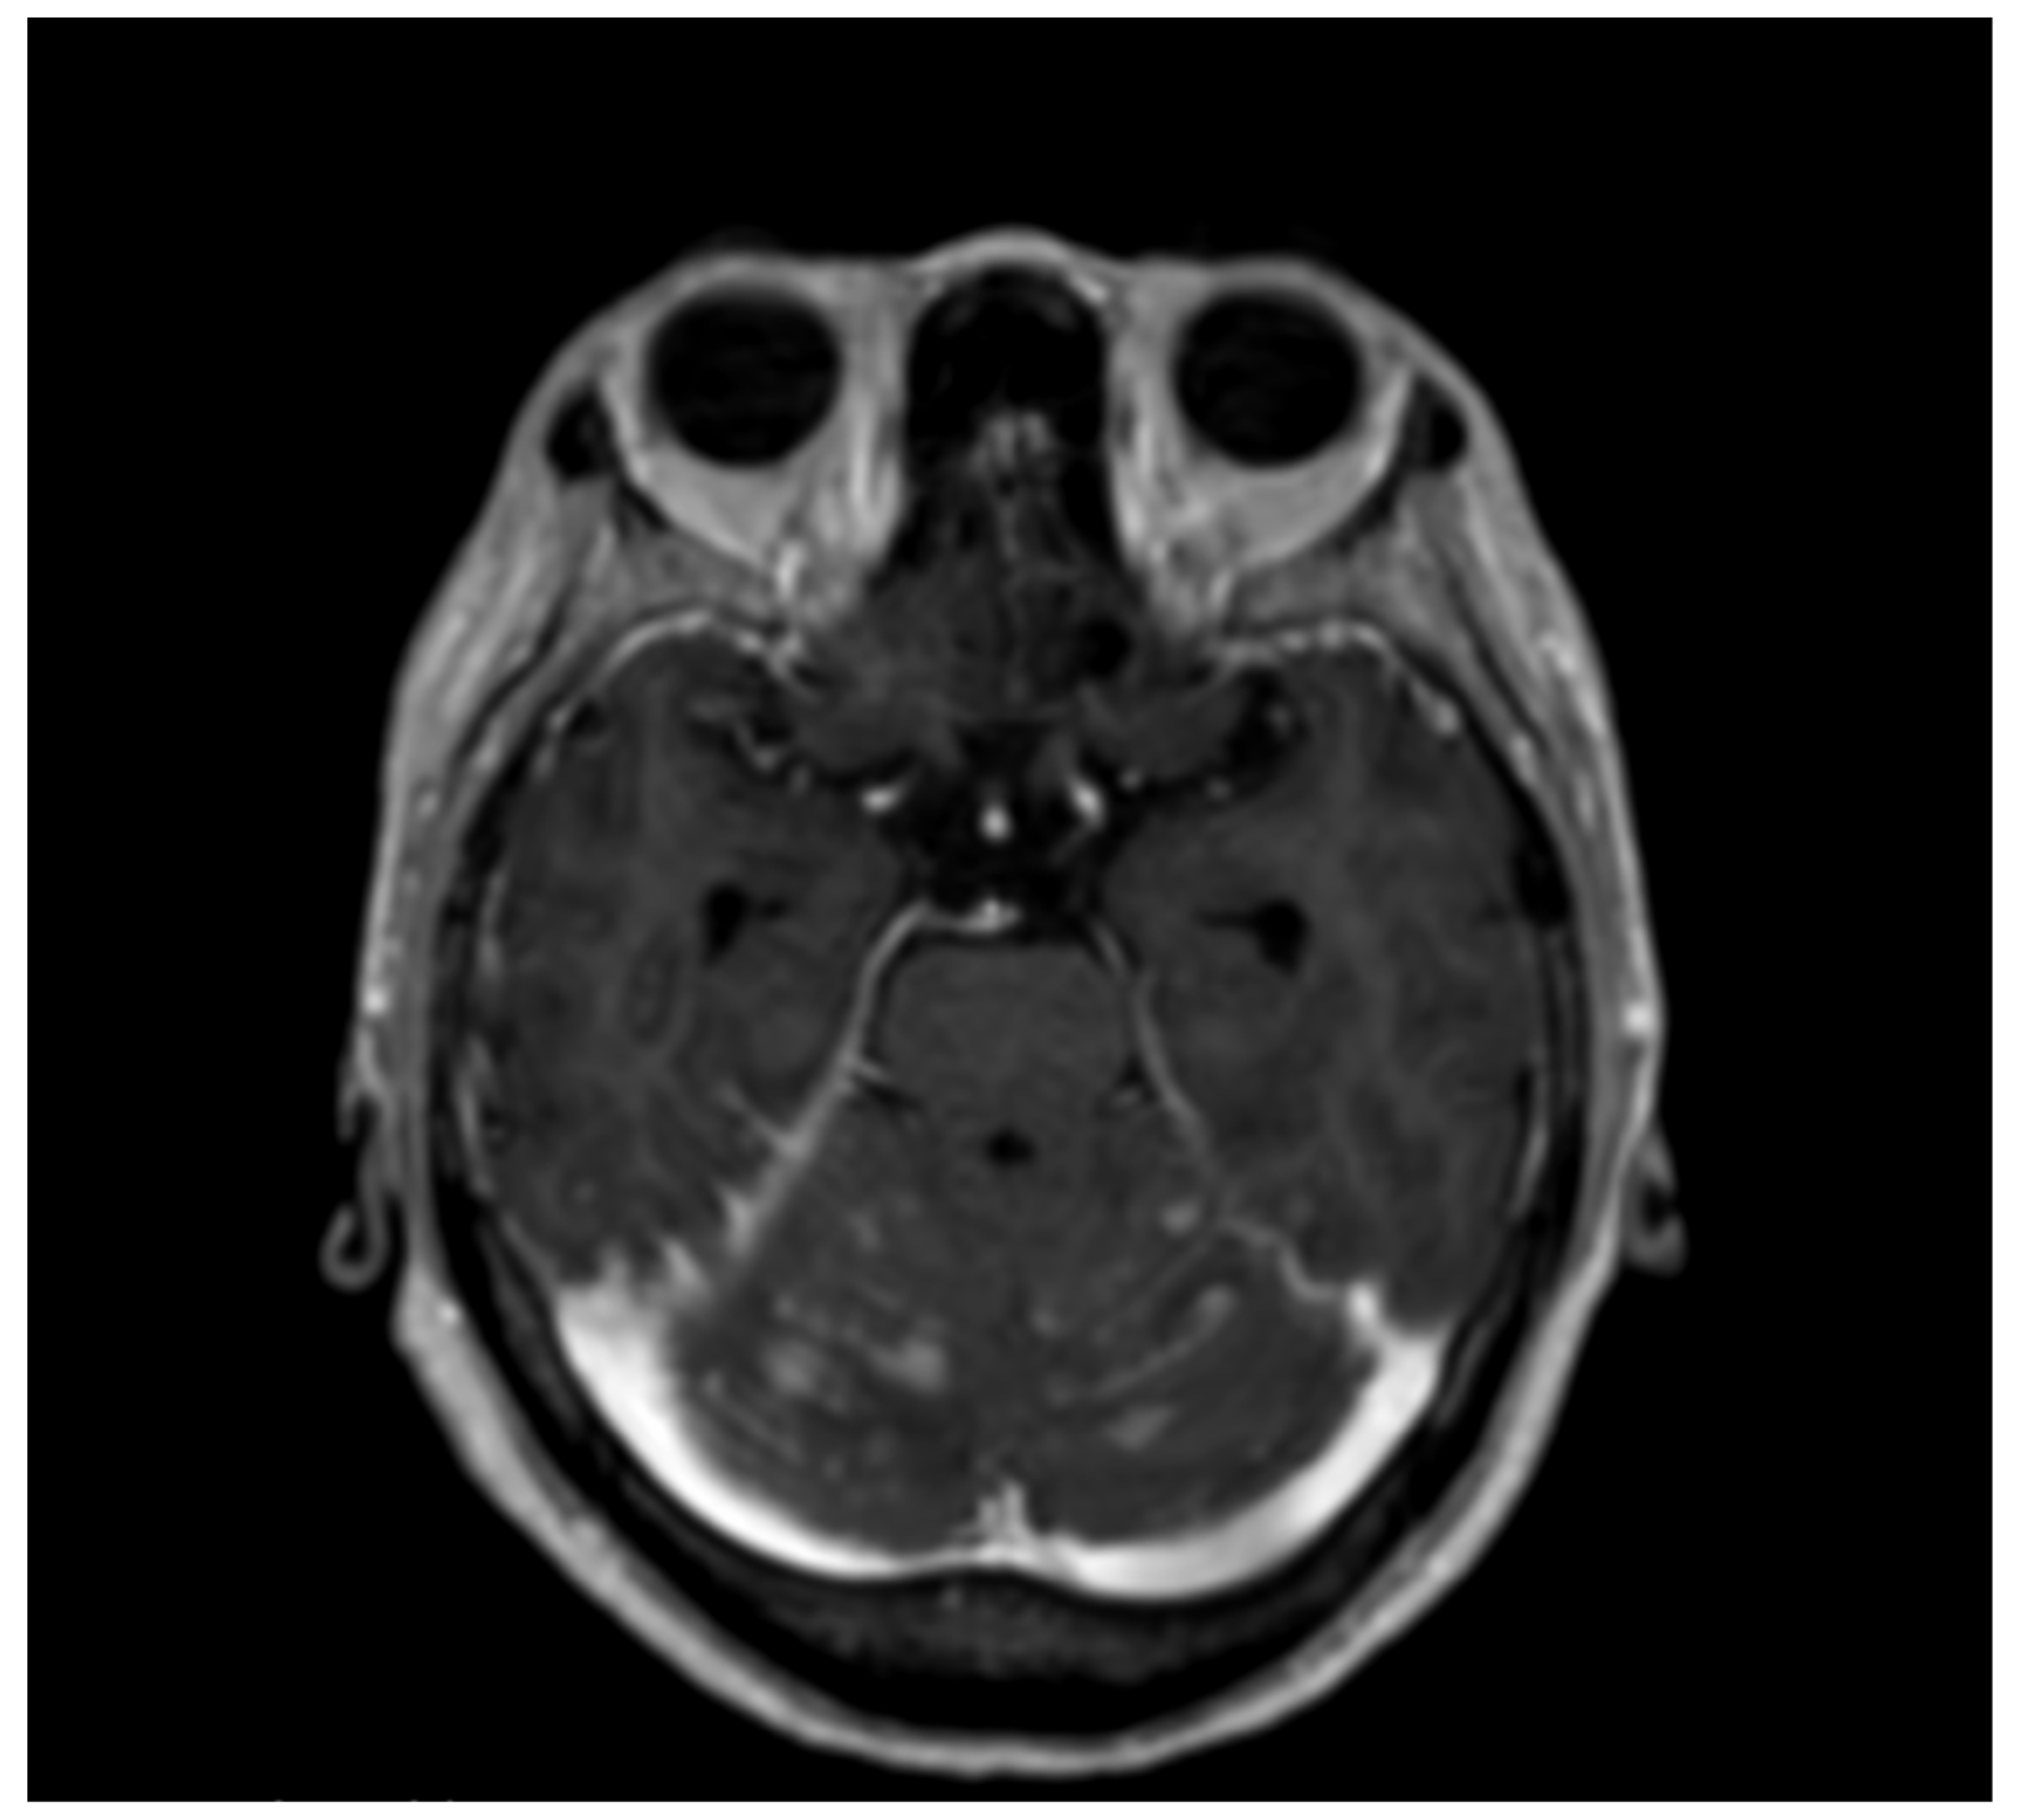

2. Case Presentation